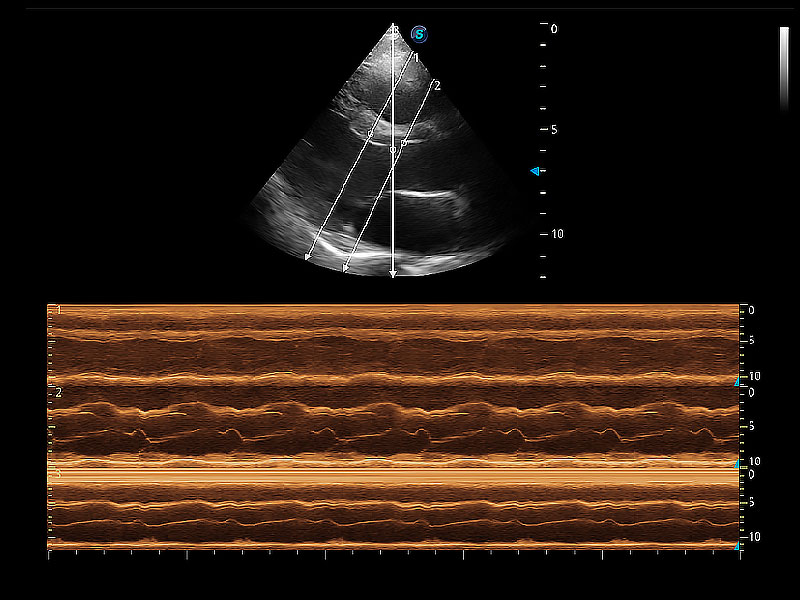

通過360度任意調(diào)節(jié)3條M型取樣線,在同一心動周期上觀察心臟不同位置的運動曲線,得到準確的心功能測量數(shù)據(jù),有效評估心肌運動及左心室功能。

ProPet 80 配備了豐富的心臟探頭群、先進的成像技術(shù)和專業(yè)的心臟測量工具,可幫助動物醫(yī)生為不同體型和生理結(jié)構(gòu)的動物提供心臟和心肌功能的全面評估。